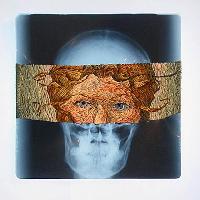

Изучение проблемы низкого качества рентгенограмм на Вашем оборудовании.

Магнитно-резонансная томография (МРТ):один из самых эффективных методов диагностики заболеваний